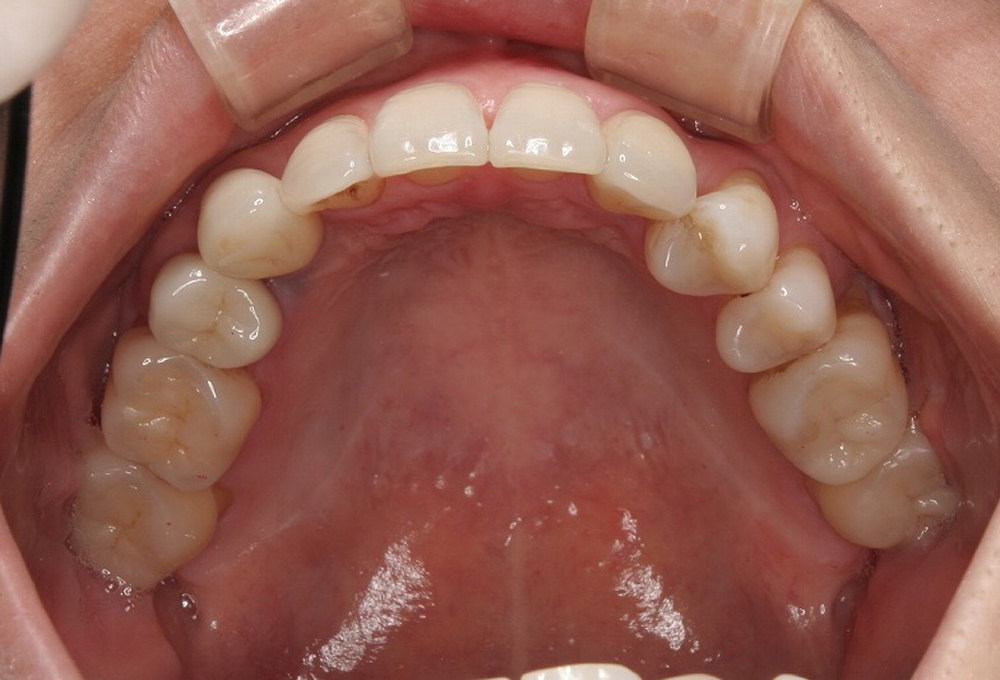

②術前 上顎